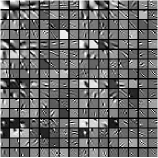

Fig. 1 shows example transforms (rows of are reshaped as patches and the first slices of such 3D patches are shown) learned from patches of an XCAT phantom [54] volume. The transform learned with in (P0) has more oriented features whereas the transform learned with shows more gradient (or finite-difference) type features (pointed by the green arrows). This behavior suggests that a single ST may not be rich enough to capture the diverse features, edges, and other properties of CT volumes. Therefore, next we consider the extension of the ST approach to a rich union of learned transforms scheme.

Fig.Β 3 presents an example of the pixel-level clustering in the central axial slice achieved with the PWLS-ULTRA method for . Since PWLS-ULTRA clusters patches, we cluster individual pixels using a majority vote among the 3D patches that overlap the pixel. Class contains most of the soft tissues; class comprises most of the bones and blood vessels; classes and have some high-contrast edges oriented along specific directions; and class mainly includes low-contrast edges. Since the clustering step (during both training and reconstruction) is unsupervised, i.e., different anatomical structures were not labeled manually, there are also a few edges with high pixel intensities included in class . The trained (3D) transforms (with ) for each cluster are also displayed in a similar manner as in Fig.Β 1. The transforms show features (e.g., with specific orientations) that clearly reflect the properties of the patches/tissues in each class.

Recall that in Section IV.F, we used the transforms learned from the patches of the XCAT phantom volume to perform reconstruction of the chest volume from helical CT data. Alternatively, one could learn the transforms from the patches of the PWLS-EP reconstruction of the helical CT data. Fig.Β 14 shows the union of transforms () learned from patches of the XCAT phantom and the PWLS-EP chest reconstruction, with . These two union of transforms display some similar types of features, and provide similar visual reconstructions in PWLS-ULTRA (with patch-based weights ) in Fig.Β 14. Thus, the transform learning algorithm extracts quite general and effective sparsifying features for images, without requiring a very closely matched training dataset.